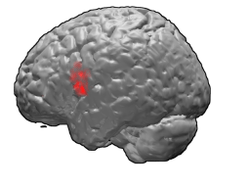

Together with left-hemisphere BA 45, the left hemisphere[1] BA 44 comprises Broca's area a region involved in semantic tasks. Some data suggest that BA44 is more involved in phonological and syntactic processing. Some recent findings also suggest the implication of this region in music perception.[2] Recent neuroimaging studies show BA44 involvement in selective response suppression in go/no- go tasks and is therefore believed to play an important role in the suppression of response tendencies.[3] Neuroimaging studies also demonstrate that area 44 is related to hand movements.[4]

Scott Flansburg of San Diego, California is a "human calculator" who can perform complex arithmetic in his head. Profiled on the TV show Stan Lee's Superhumans, his brain was scanned using fMRI while doing complex calculations, which showed brain activity in this region was absent. Instead there was activity somewhat higher from area 44 and closer to the motor cortex.[5]